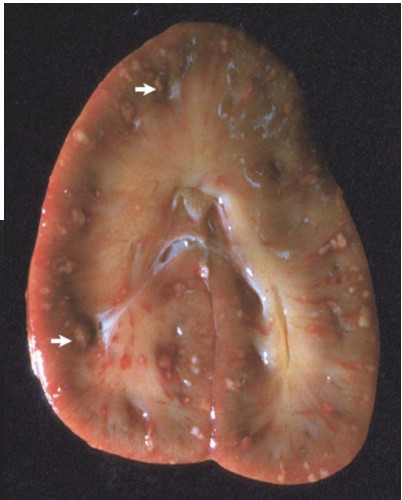

What is this lesion and why are the kidneys susceptable ?

Kidney Infarction

The kidneys are susceptable

1. Arterial blood supply to the cortex is terminal

- few anastomoses of the renal blood vessels

2. Receives a large portion of overall blood volume 25%